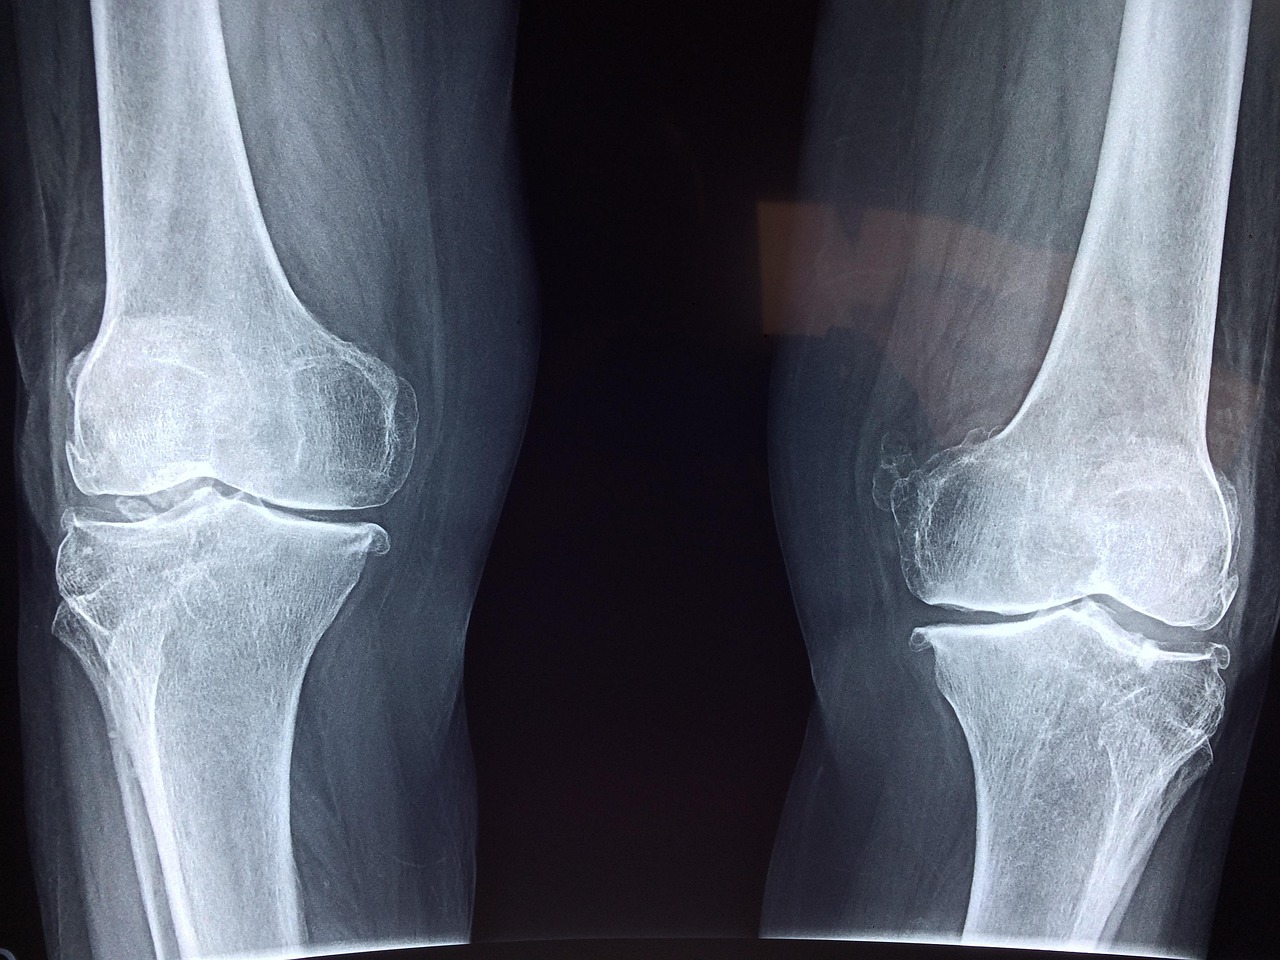

수술 전에 필요한 검사는 신체 상태를 평가하고 최적의 치료 계획을 세우기 위해 꼭 필요합니다. 혈액 검사, 엑스레이 또는 MRI 촬영 등을 통해 무릎 관절의 손상 정도를 파악하며, 심장이나 폐 기능도 함께 점검해 안전하게 수술할 수 있는지 판단합니다. 그리고 의사와의 상담에서는 기존 질환 유무, 복용 중인 약물, 알레르기 여부 등을 상세히 알려야 하며, 어떤 인공관절 재질과 디자인이 적합한지도 논의하게 됩니다.